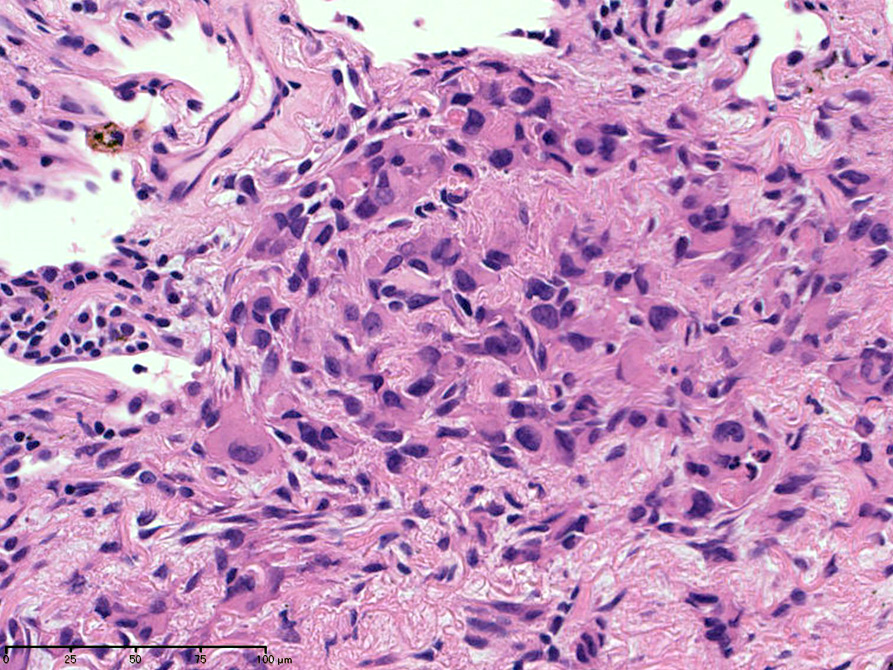

左図:腺腔様の裂隙が胞巣内にみられ, 凍結標本だと腺癌との区別がむずかしい。

右図:多型細胞や異型細胞が出現。核分裂像も異常に見える。